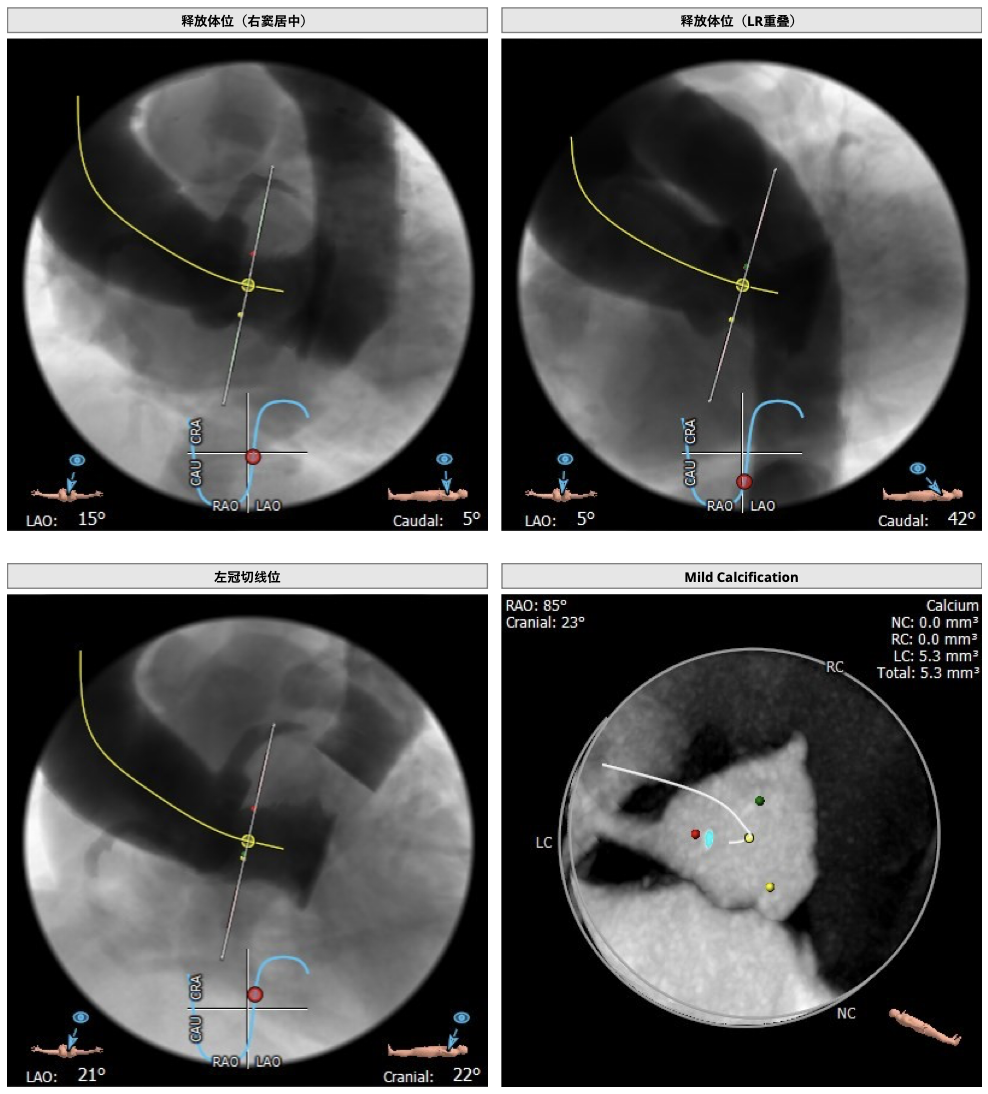

主动脉CT

难点分析:

*患者为四叶瓣,单纯返流,瓣膜锚定具有有一定难度,对释放瓣膜的把控要求高;

*右冠高度可,但左冠高度稍低,具有一定冠脉风险;

*心脏角度略大,释放瓣膜时,瓣膜与瓣环同轴性差。

制定策略:

经分析研判,拟从右侧股动脉穿刺入路,结合患者返流特点与主动脉根部结构,选用L26号的VenusA-Valve瓣膜,使用VenusA-Plus可回收输送系统,确保手术安全和瓣膜的稳定释放,必要时可使用圈套器辅助瓣膜释放,瓣膜释放后结合造影和超声情况,决定是否后扩。